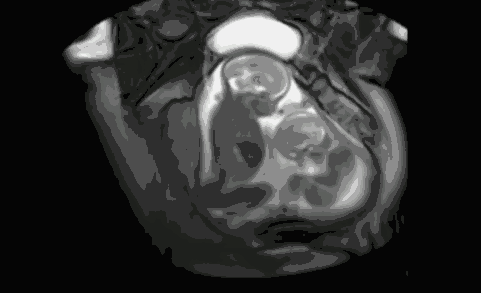

胚胎移植在子宫有动图,胚胎着床图片

不是每个子宫腔都张开臂膀拥抱胚胎的

胚胎着床图片

胚胎移植着床全过程图